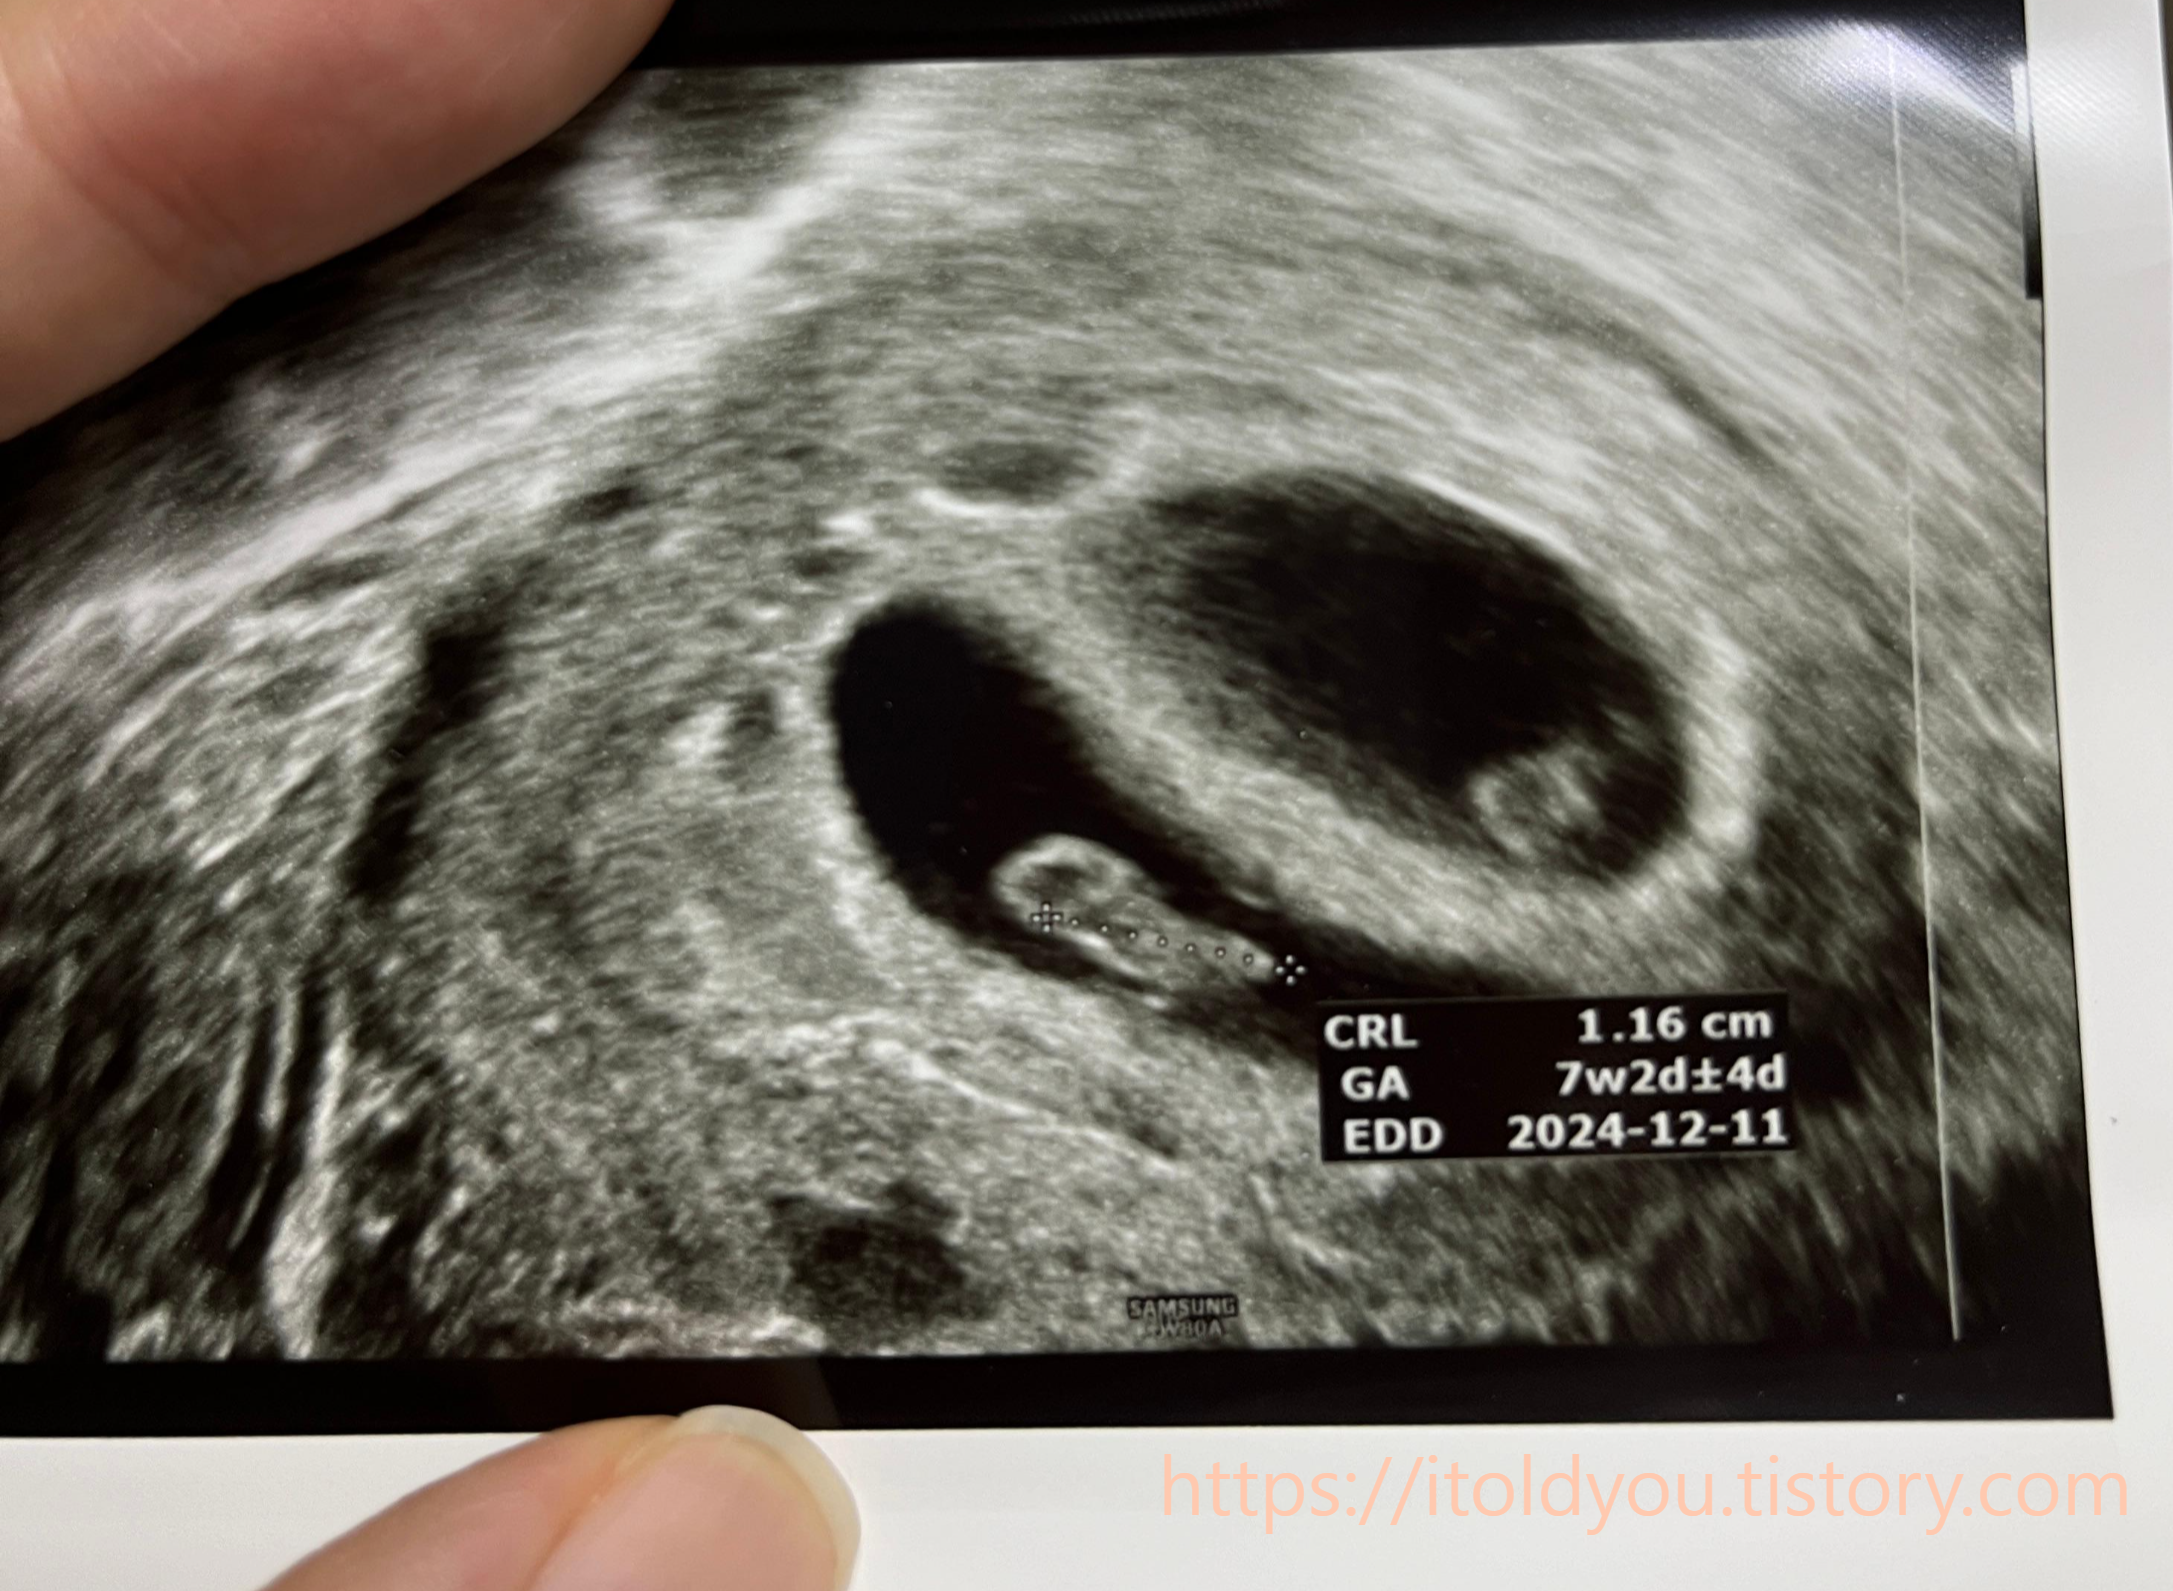

8주에서 9주쯤 넘어가던 사이 (난임병원은 12주 지나 졸업)

응급실에서 다행이 아기들은 이상없고 피고임이 좀 흘러나온거같으니

유산방지주사 맞고 날이밝으면 진료보는 난임병원 가보라고 하셧다

다행이 별 탈 없이 난임병원은 졸업을 했고